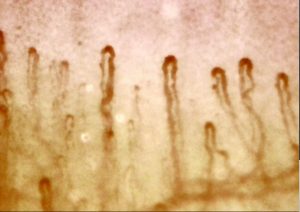

血流スコープの特徴は、

自分の血流の状態をその場で確認できることです。

普段は感じにくい体の変化も、

視覚的に確認することで、より理解しやすくなります。

・流れの速さ

・赤血球の動き

・血流のスムーズさ

こうした変化を“見る”ことで、

体の状態への意識も高まります。